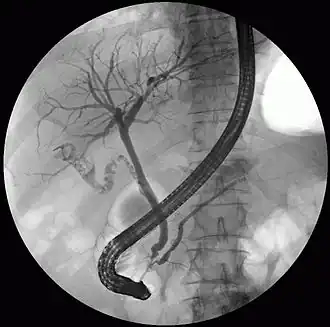

ERCP image showing the pancreatic duct and biliary tree. -